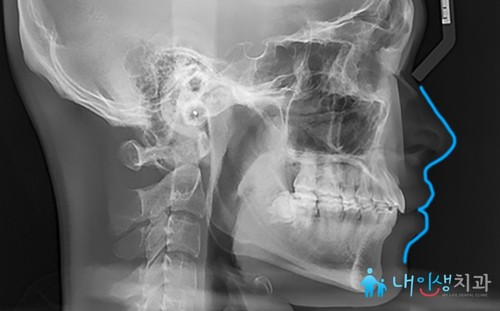

<진료 종료>

서초치아교정을 시작한 뒤

1년 5개월이 지나고

진료를 최종 마무리한 모습입니다.

X-ray 전후 사진도 함께 살펴볼게요.

뻐드러졌던 앞니 각도가

자연스럽게 맞춰진 것을 확인할 수 있습니다.

틀어진 치아로 인해 입술이 많이 돌출되고

입을 다문 모습도 부자연스러웠는데

교정 치료를 통해 말끔하게

해결된 모습이에요.